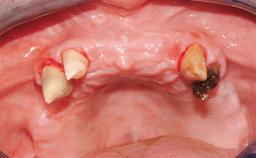

A 63-year-old male patient was referred for a consultation and treatment of partial edentulism in the maxilla. The patient presented with residual anterior teeth and declined a partial removable prosthesis. He reported that the maxillary posterior teeth had been extracted due to mobility and periodontal disease two months before the consultation. The patient’s chief complaint was that his residual maxillary teeth were mobile and that he was unable to chew. The patient’s desire was a stable and comfortable fixed maxillary rehabilitation. The patient was a light smoker (fewer than 10 cigarettes/ day), and his medical history was without significant findings. He was not on any regular medication at the time of consultation. The extraoral examination revealed a normal physiognomy with a correct distribution of the facial thirds. The patient presented a low lip line, and the transition line between teeth and soft tissues was not exposed during a forced smile.

Soft Tissue Anatomy Intact Defective

Bone Volume Horizontally and vertically sufficient Horizontally deficient Deficient vertically or deficient vertically AND horizontally